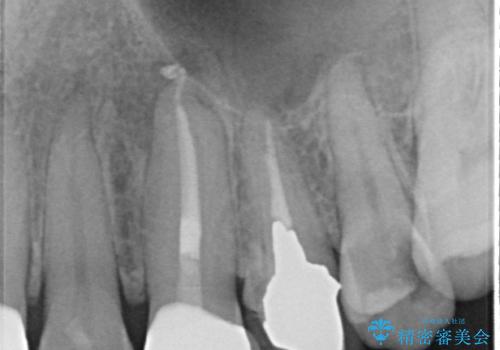

▶左上中切歯

土台を再度丁寧に整え、オールセラミッククラウンにて補綴